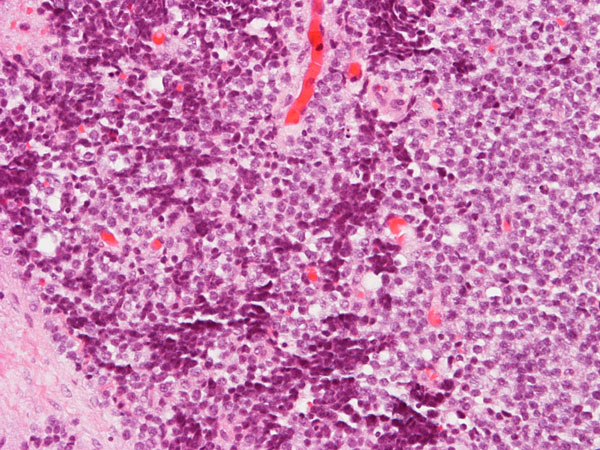

Download Homer Wright Rosettes Ewing Sarcoma Pictures. In histopathology, a palisade is a single layer of relatively long cells, arranged loosely perpendicular to a surface and parallel to each other. Neuroblastoma, homer wright rosettes are circular groupings of dark tumor cells surrounding pale neurofibrils (small blue cell tumors from neural crest ectoderm).

Последние твиты от homer wright rosette (@h_wright_rosset). Neuroblastoma, homer wright rosettes are circular groupings of dark tumor cells surrounding pale neurofibrils (small blue cell tumors from neural crest ectoderm). Ewing's sarcoma & pnet form a spectrum with es being less differentiated.